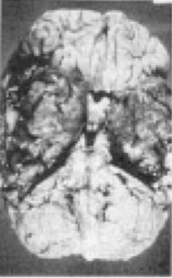

Gambar ini menunjukkan MRI Potongan koronal pada pasien dengan lesi massa. meskipun MRI tidak mendiagnosis, manakah patogen yang sering menunjukkan gambaran tersebut?

A. Aspergillus

B. Histoplasma

C. Cryptococcus

D. Macromycosis

A